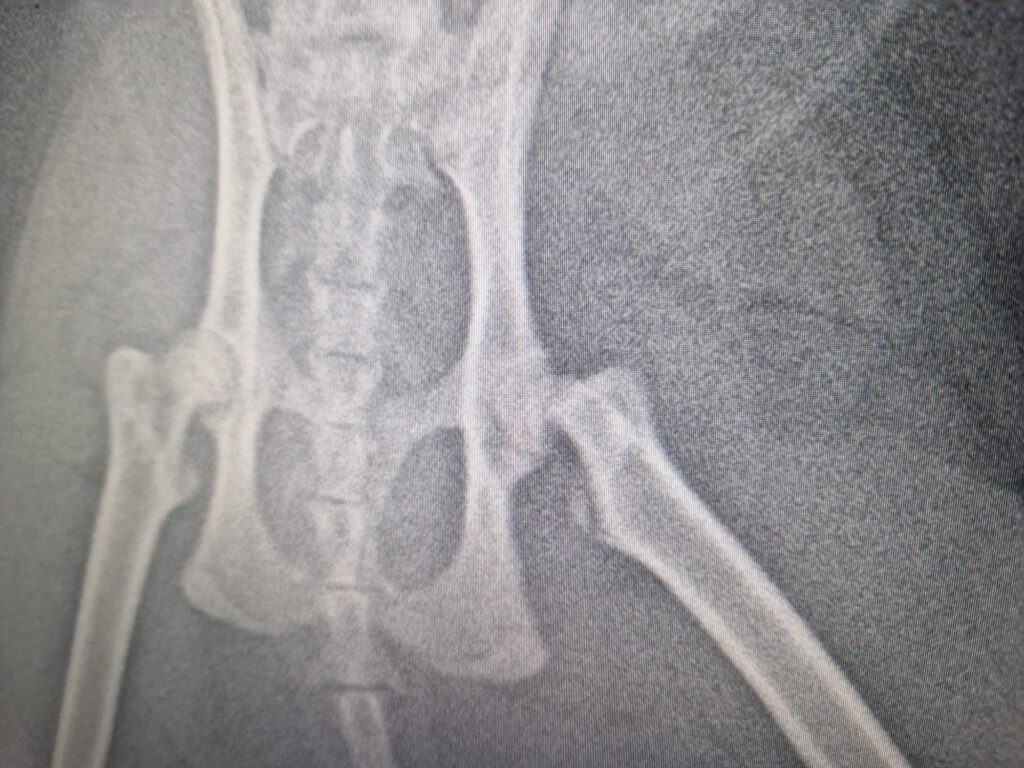

Der hübsche Kerl kam mit starken Schmerzen in der Hinterhand in eine Tierarztpraxis. Er lief lahm, belastete das Bein kaum noch. Auf dem Röntgenbild zeigte sich schließlich das Problem:

Der Femurkopf hat sich vom Oberschenkelhals gelöst.

Eine schwere orthopädische Erkrankung, die man vor allem bei jungen, männlichen und übergewichtigen Katzen sieht.

Eine mögliche sinnvolle Behandlung ist eine sogenannte Femurkopf-Hals-Resektion. Dabei wird der Hüftkopf entfernt, damit sich ein neues, schmerzfreies „Ersatzgelenk“ bilden kann. Katzen kommen mit dieser Operation in der Regel sehr gut zurecht und können danach wieder schmerzfrei laufen.